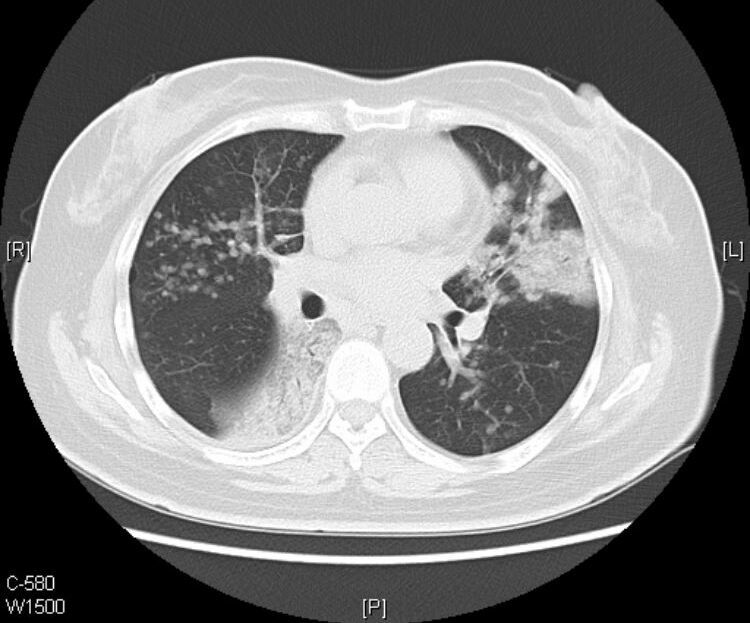

接着看她往下的CT层面:

从CT片上我们可以看到:老人的黏液腺癌还发生了气道转移。

CT提示气道播散的征象包括:多发小叶中心结节,分支模糊呈树芽征,通常边界不清,可见磨玻璃影。

1.气道播散形成的结节呈聚集分布,可以融合增大,有时也可形成空腔。

2.当转移灶远离原发灶时,所形成结节多分布于肺叶下部。